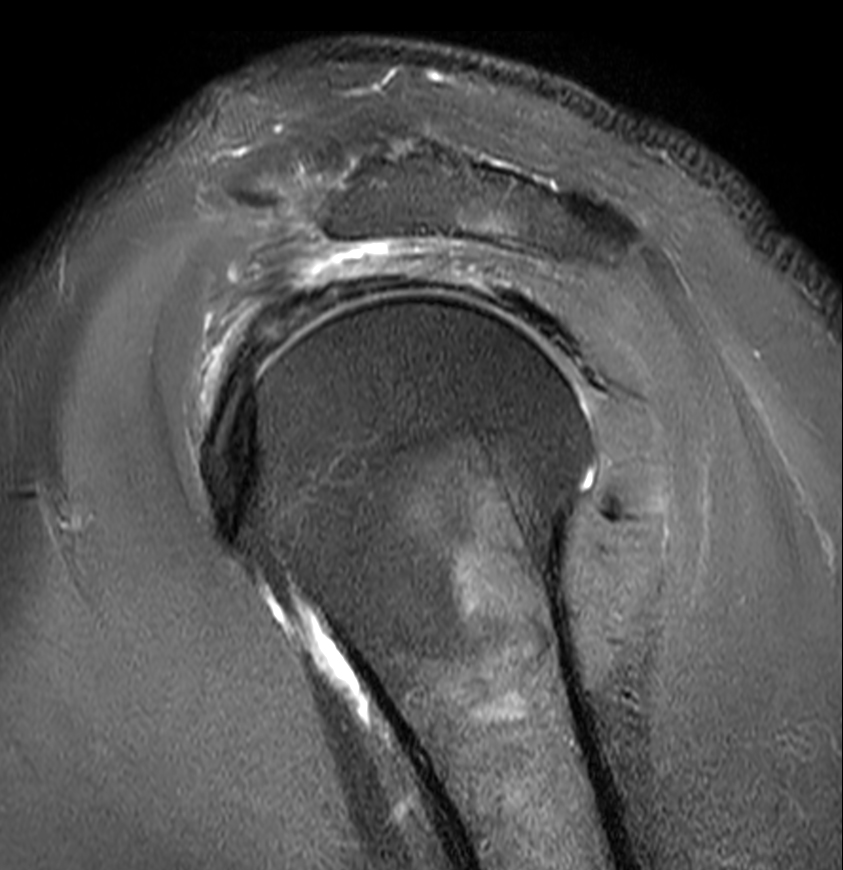

High resolution imaging with the dS 16ch Shoulder coil and Compressed SENSE